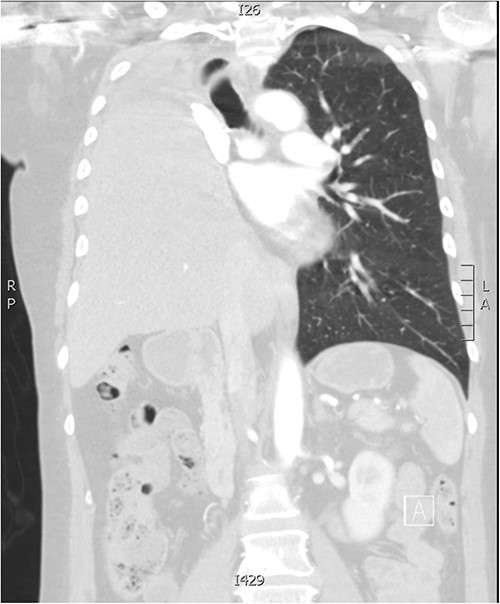

The patient had an uneventful post-operative course and subsequently discharged home. Follow-up imaging shows complete elevation of the liver into the right thoracic cavity (Fig. 2). On review 21 years post-initial diagnosis, she remains asymptomatic and disease-free.

Follow-up CT imaging demonstrating complete migration of the liver into the right thoracic cavity.

Post-pneumonectomy hemidiaphragm elevation and mediastinal shift affects the position of vital organs, such as shifting of the heart into the post-pneumonectomy space. A rare post-pneumonectomy syndrome can arise, where there is excessive mediastinal shift resulting in airway obstruction. Iatrogenic harm can be caused, as reported in a case of inadvertent perforation of the right ventricle during blind insertion of a chest tube [4]. In this patient, there is complete migration of the liver into the post-pneumonectomy space, a rarely documented complication. Phrenic nerve resection likely explains the excessive laxity noted in the hemidiaphragm and consequent severe eventration.